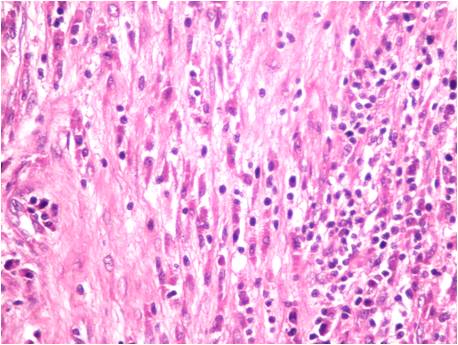

Inflammatory myofibroblastic tumor of the gall bladder: a rare case report

Inflammatory myofibroblastic tumor (IMT) is a benign proliferation of myofibroblasts, which is prone to recurrence, persistent local growth as well as malignant transformation. The commonest site reported in the biliary tree is the extrahepatic bile duct. Gall bladder is a rare site for the development of an IMT. We report a case of an inflammatory myofibroblastic tumor of the gall bladder in an adult female with coextistent cholecystitis and cholelithiasis. It is important to acknowledge this entity since it can mimic malignancy.References